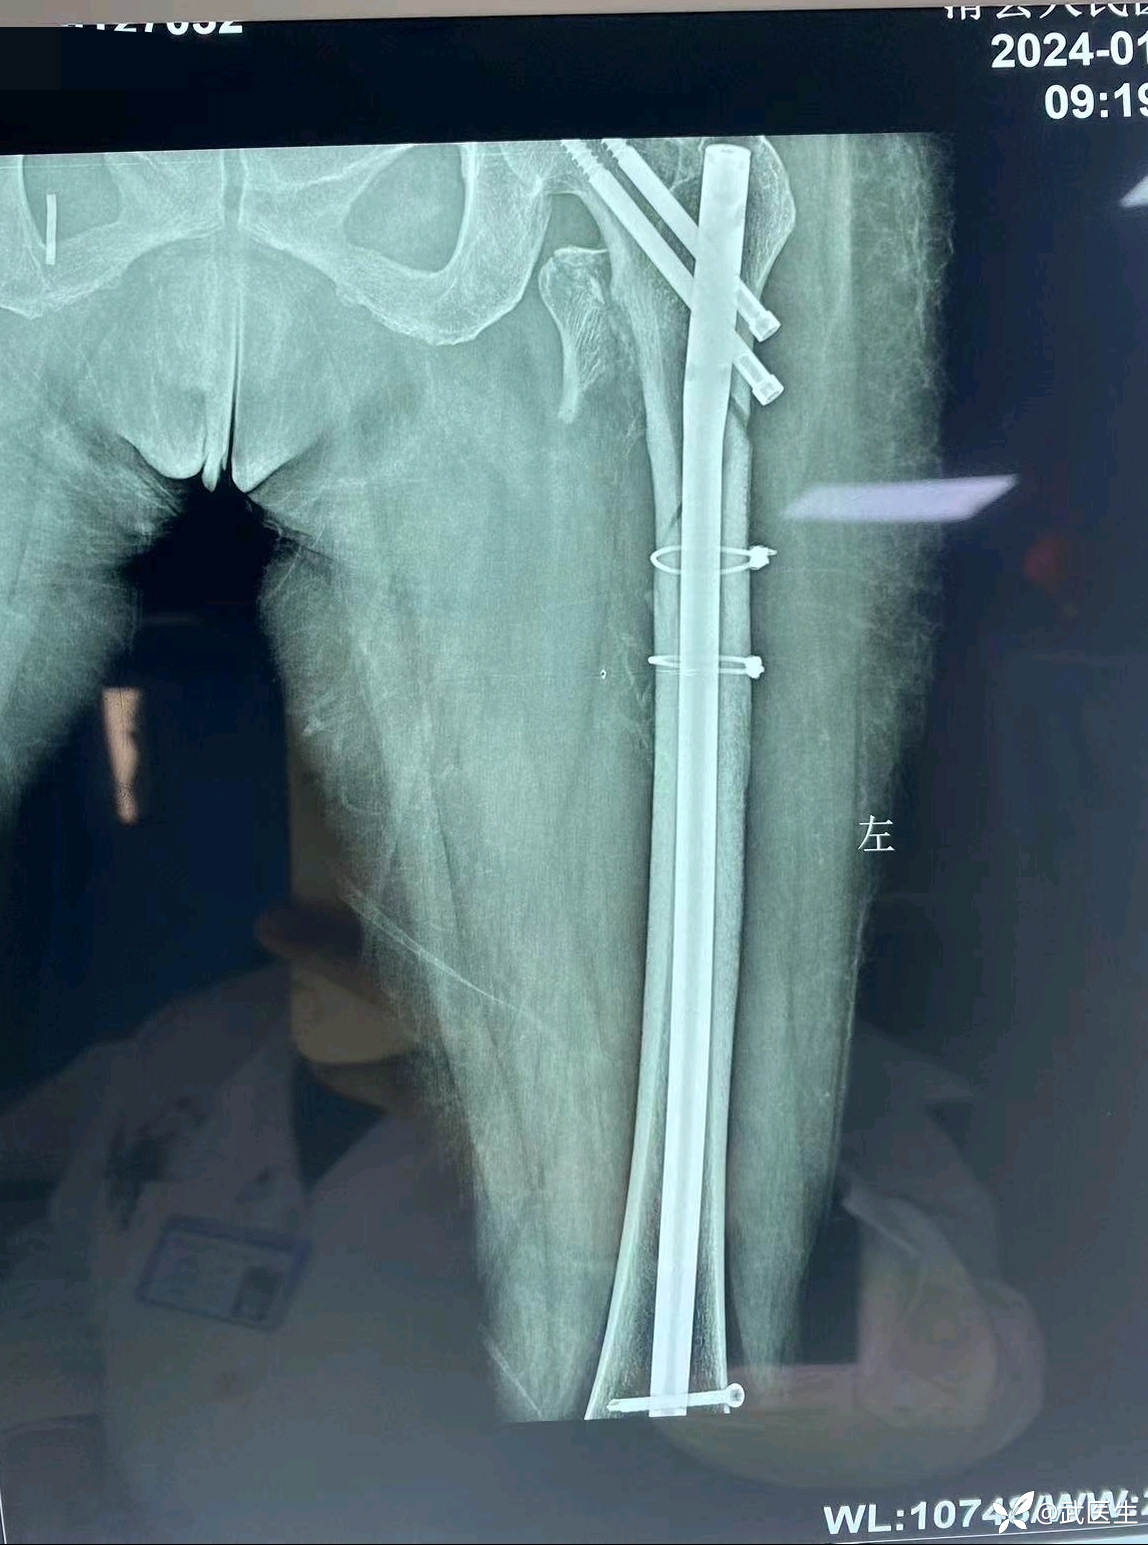

最终如下

还行吧,顶天立地,断端对位良好,头颈钉偏后置入但都在头内固定牢固可靠。

术后六周复诊如下

骨痂不明显,断端对位良好。